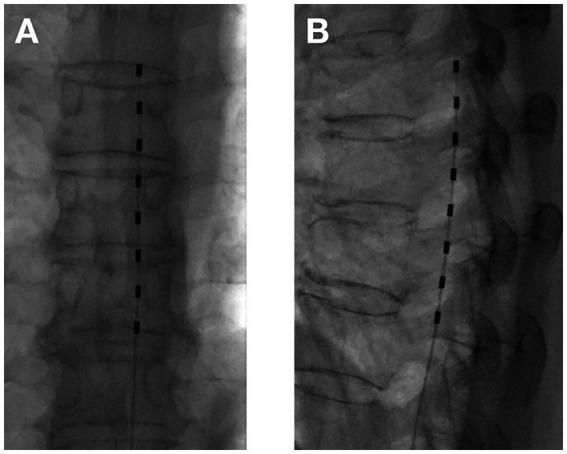

Zoster-associated pain (ZAP) is a common complication after herpes zoster infection. In recent years, conventional temporary dorsal column stimulation (tDCS) has been widely used nationally and internationally as a safe and effective minimally invasive treatment for ZAP. It has also been shown that temporary dorsal nerve root stimulation (tDNRS) may also be an effective treatment for ZAP. However, there is no direct clinical comparison between the newer tDNRS and the conventional tDCS.

To compare the procedure time, radiation dose, efficacy and cost of the tDNRS and tDCS for the treatment of ZAP. And the complications of the two surgical modalities were recorded.

Eighty patients with ZAP who attended the pain department of the Second Affiliated Hospital of Guangxi Medical University from January 2022 to July 2023 were selected. They were divided into tDNRS group ( = 40) and tDCS group ( = 40) by using random number table method. The operation time, radiation dose, number of electrodes used, cost of medical consumables, and number of postoperative electrical stimulation adjustments were recorded for each case, and the patients' pain level, sleep quality, quality of life, and overall efficacy were analysed and compared at preoperative (T0), 1 week (T1), 1 month (T2), 2 months (T3) and 3 months (T4) after the operation.

A total of 76 patients were finally enrolled, 38 in the tDNRS group and 38 in the tDCS group. During the 3-month follow-up period, all patients showed a significant decrease in Numerical Rating Scale (NRS) and Pittsburgh Sleep Quality Index (PQSI) scores and a significant increase in quality of life (QL-Index scale) scores after treatment with both methods. And there was no statistically significant difference between the two methods. However, patients who received tDNRS had a significantly shorter operative time and less intraoperative radiation exposure than those who received tDCS ( < 0.0001), and the mean number of postoperative stimulation parameter adjustments and the cost of medical consumables were significantly lower than those in the tDCS group ( < 0.0001).

Both tDNRS and tDCS were effective in the treatment of ZAP, but tDNRS had the advantages of more precise coverage, shorter procedure time, less radiation exposure, fewer electrical stimulation adjustments, and lower cost.